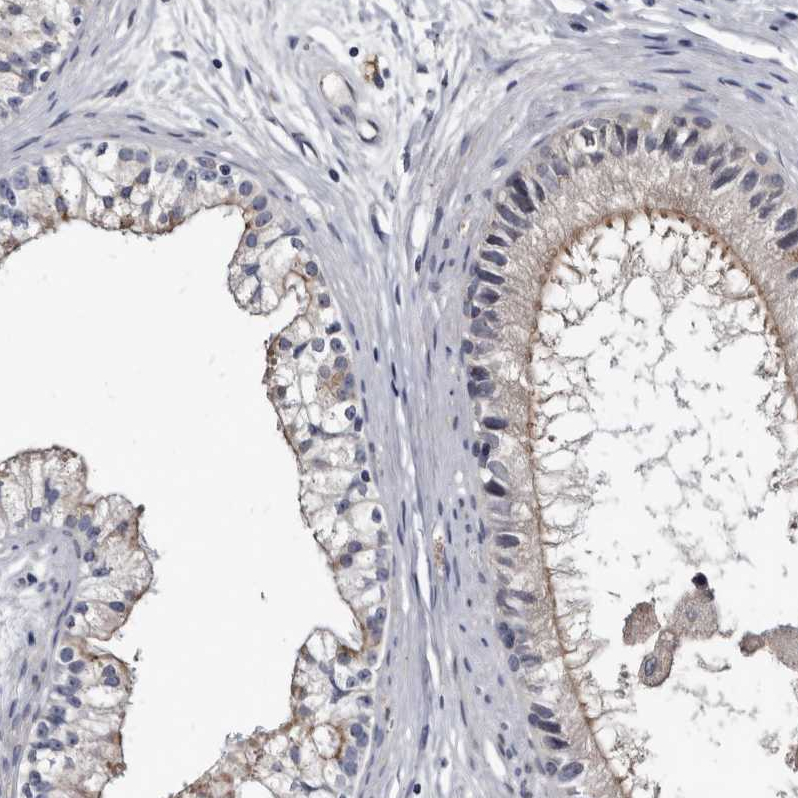

Immunohistochemical staining of human rectum shows strong positivity in apical membrane in glandular cells.